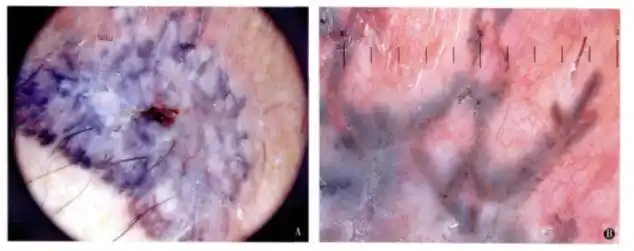

阴囊是男性的外生殖器官,位于阴茎根部下方,是一个薄而柔软的多层结构